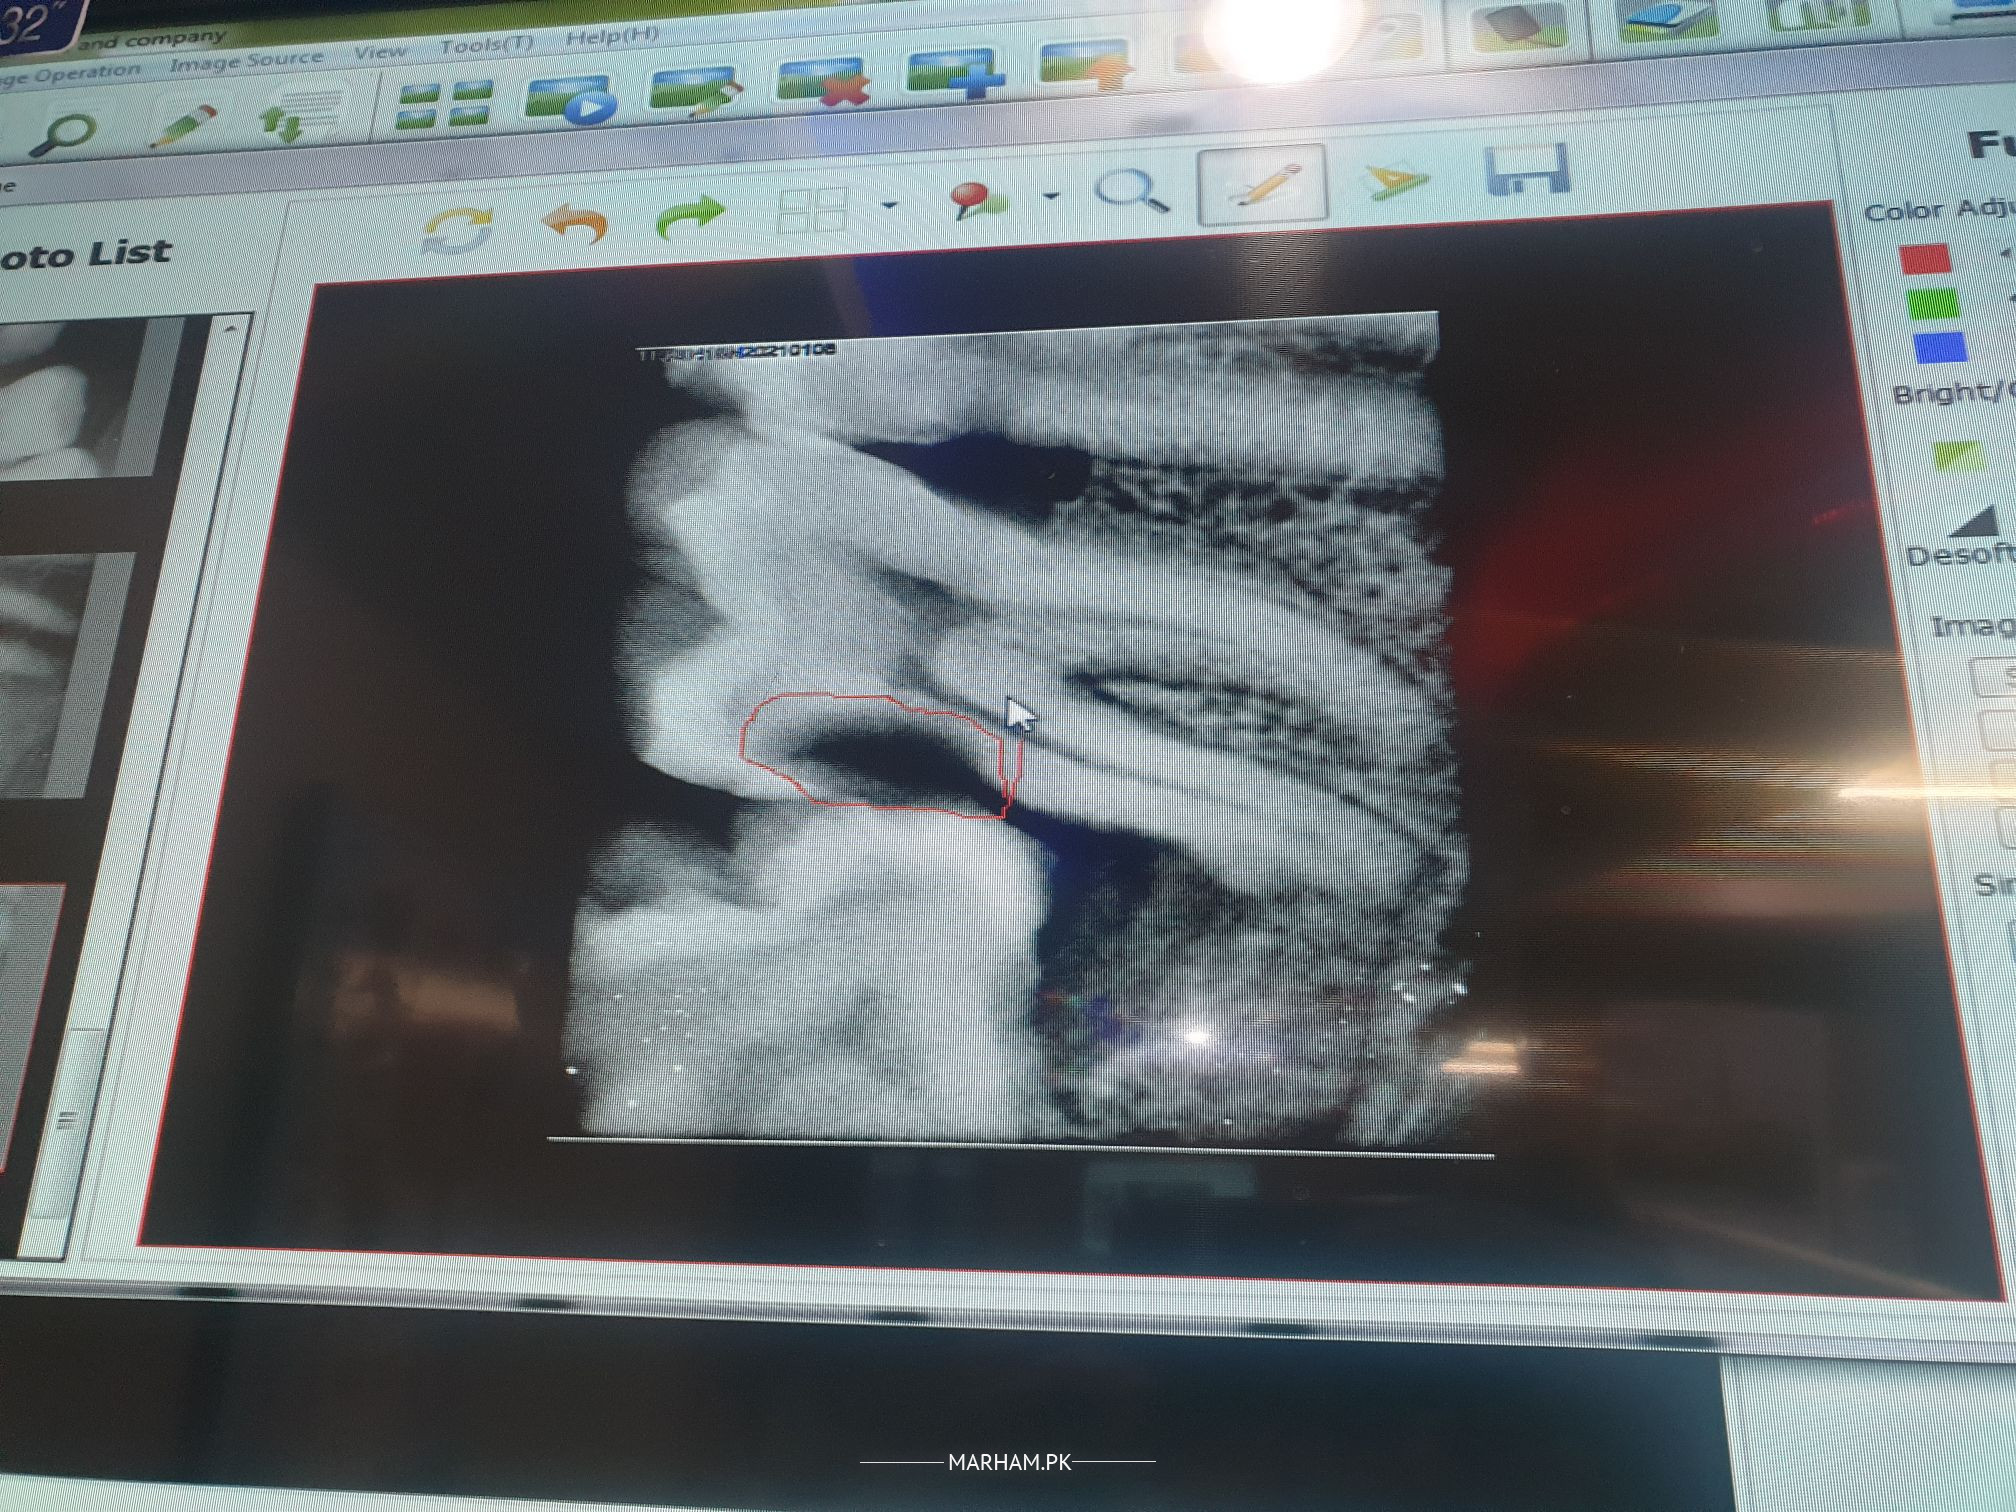

assalam o alaikum mujhe doctor ne extraction ka kaha hai kindly confirm ker dain kon sa tooth extract ho ga last wala ya 2nd wala. me xray attach ker raha ho

last wala and second last mein endo plus filing k option ha bs bcx usk distally bh bone loss bht ziada ha

most probably dono remove hon gae

it's hard to say k apka 2nd last tooth safe ho jae, but last wala is confirmed extraction.

further confirmation for 2nd last can be done after the removal of last tooth

Aoa. The last tooth has to be extracted. Second last may be saved by root canal treatment but after clinical assessment. Regards

you need to visit a consultant for extraction of third and 2nd molar both .

Wa Alaikum Assallam. Dono teeth main issue hai. Basically last wala tooth apni jagah per sahi nahin aya jis ki waja sey usney 2nd last walay ko bhi pressure dekey kharab kerliya hai. Pehley last wala nikalwaein. Uskey baad 2nd last walay ko dobara examine kerwaein. Per condition wise 2nd last bhi sahi nahin hai.

Hi,last one will be surely extracted and second one needs to be examined then decide if it can be saved by RCT or extraction has to be done.

Last tooth extraction and 47 need RCT

dono ke extraction he ho ge keu ky second last mai root caries hn

2nd last needs extraction. last molar may be left alone until it cause any problems